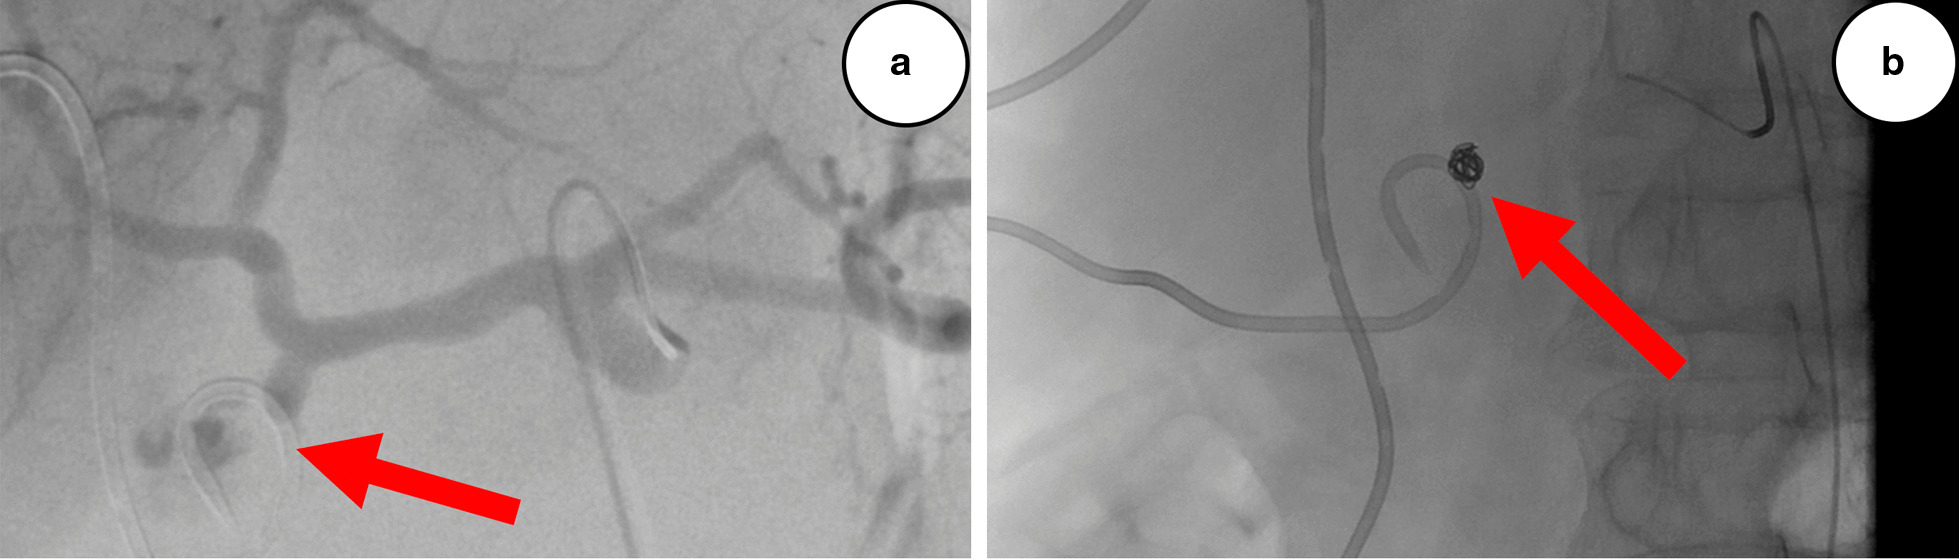

On POD 26, the patient presented blood in both drains and bloody stools. Endoscopy of the gastrojejunostomy (the hepaticojejunostomy could not be visualized because the reconstruction was made on a long Roux loop) and a CT angiography (Fig. 2a) could not localize any evidence of bleeding. The patient was hemodynamically stable, and there was only discrete evidence of bleeding on the hemoglobin curve, presently 89 g/L (98 g/L on the day before and had been stable at approximately 100 g/L without transfusions during the entire preceding postoperative period). Two units of erythrocytes were administered, and on the next day the hemoglobin level was 107 g/L. On POD 28, the patient had a new episode of bleeding in both drains and multiple bloody stools. A repeat endoscopy and CT angiography (Fig. 2b) were both unremarkable. Besides discrete pallor and tiredness, the patient was still in good clinical condition with stable vitals; hemoglobin level was 86 g/L, and after one erythrocyte transfusion it was 93 g/L. Because of continuous bleeding but no identified source, an empiric suspicion of intraabdominal bleeding was raised, and a conventional selective angiography was performed on the next day, revealing a contrast leakage from the gastroduodenal artery (GDA) stump (Fig. 3a), which was coiled successfully (Fig. 3b). The biliary drain had to be changed because it was completely obliterated by blood clots. The clinical conclusion was that of a grade B hemorrhage, and that the blood from the GDA stump had traveled through the insufficient hepaticojejunostomy into the biliary tree and small intestine, causing the presence of blood in both drains and bloody stools (Fig. 4). During the next couple of days, the intraabdominal drain was removed, and the patient was discharged with the biliary drain in situ on POD 45. Her hemoglobin level was 93 g/L, and inflammatory parameters and liver function tests were unremarkable.

Fig. 3.

a Conventional selective angiography on postoperative day 29 showing contrast leakage (arrow) from the gastroduodenal artery stump. b Successfull coiling (arrow) with endovascular technique

A combination of extra- and intraluminal presence of blood is not a spectacular finding in the presence of an insufficient hepaticojejunostomy and a transhepatic drain. Also, bleeding from the GDA stump is the most frequent origin of PPH [9], but it is the underlying mechanism in our case that is exceptional. The presentation initially led us to believe that the source of bleeding was intraluminal. Given our knowledge of the biliary anastomotic leak, the bloody discharge from the abdomen was assumed to have leaked into the peritoneal cavity through the insufficient hepaticojejunostomy. In fact, it was the other way around—a long stump of GDA adjacent to the anastomotic defect was bleeding into the biliary tree and small intestine.

In a recent systematic review, CT angiography and conventional angiography had the same sensitivity (67 versus 69%) for identifying the origin of late PPH [9]. In our case, two consecutive CT angiographies were negative. Only when a catheterization of the celiac trunk was made could we identify the source of bleeding. It was confirmed by a selective catheterization of the GDA stump. The first episode in our patient could be considered a sentinel bleed [10]. Some institutions recommend an aggressive approach to sentinel bleeds; however, their prognostic value and the role of prophylactic treatment remain unclear [11].